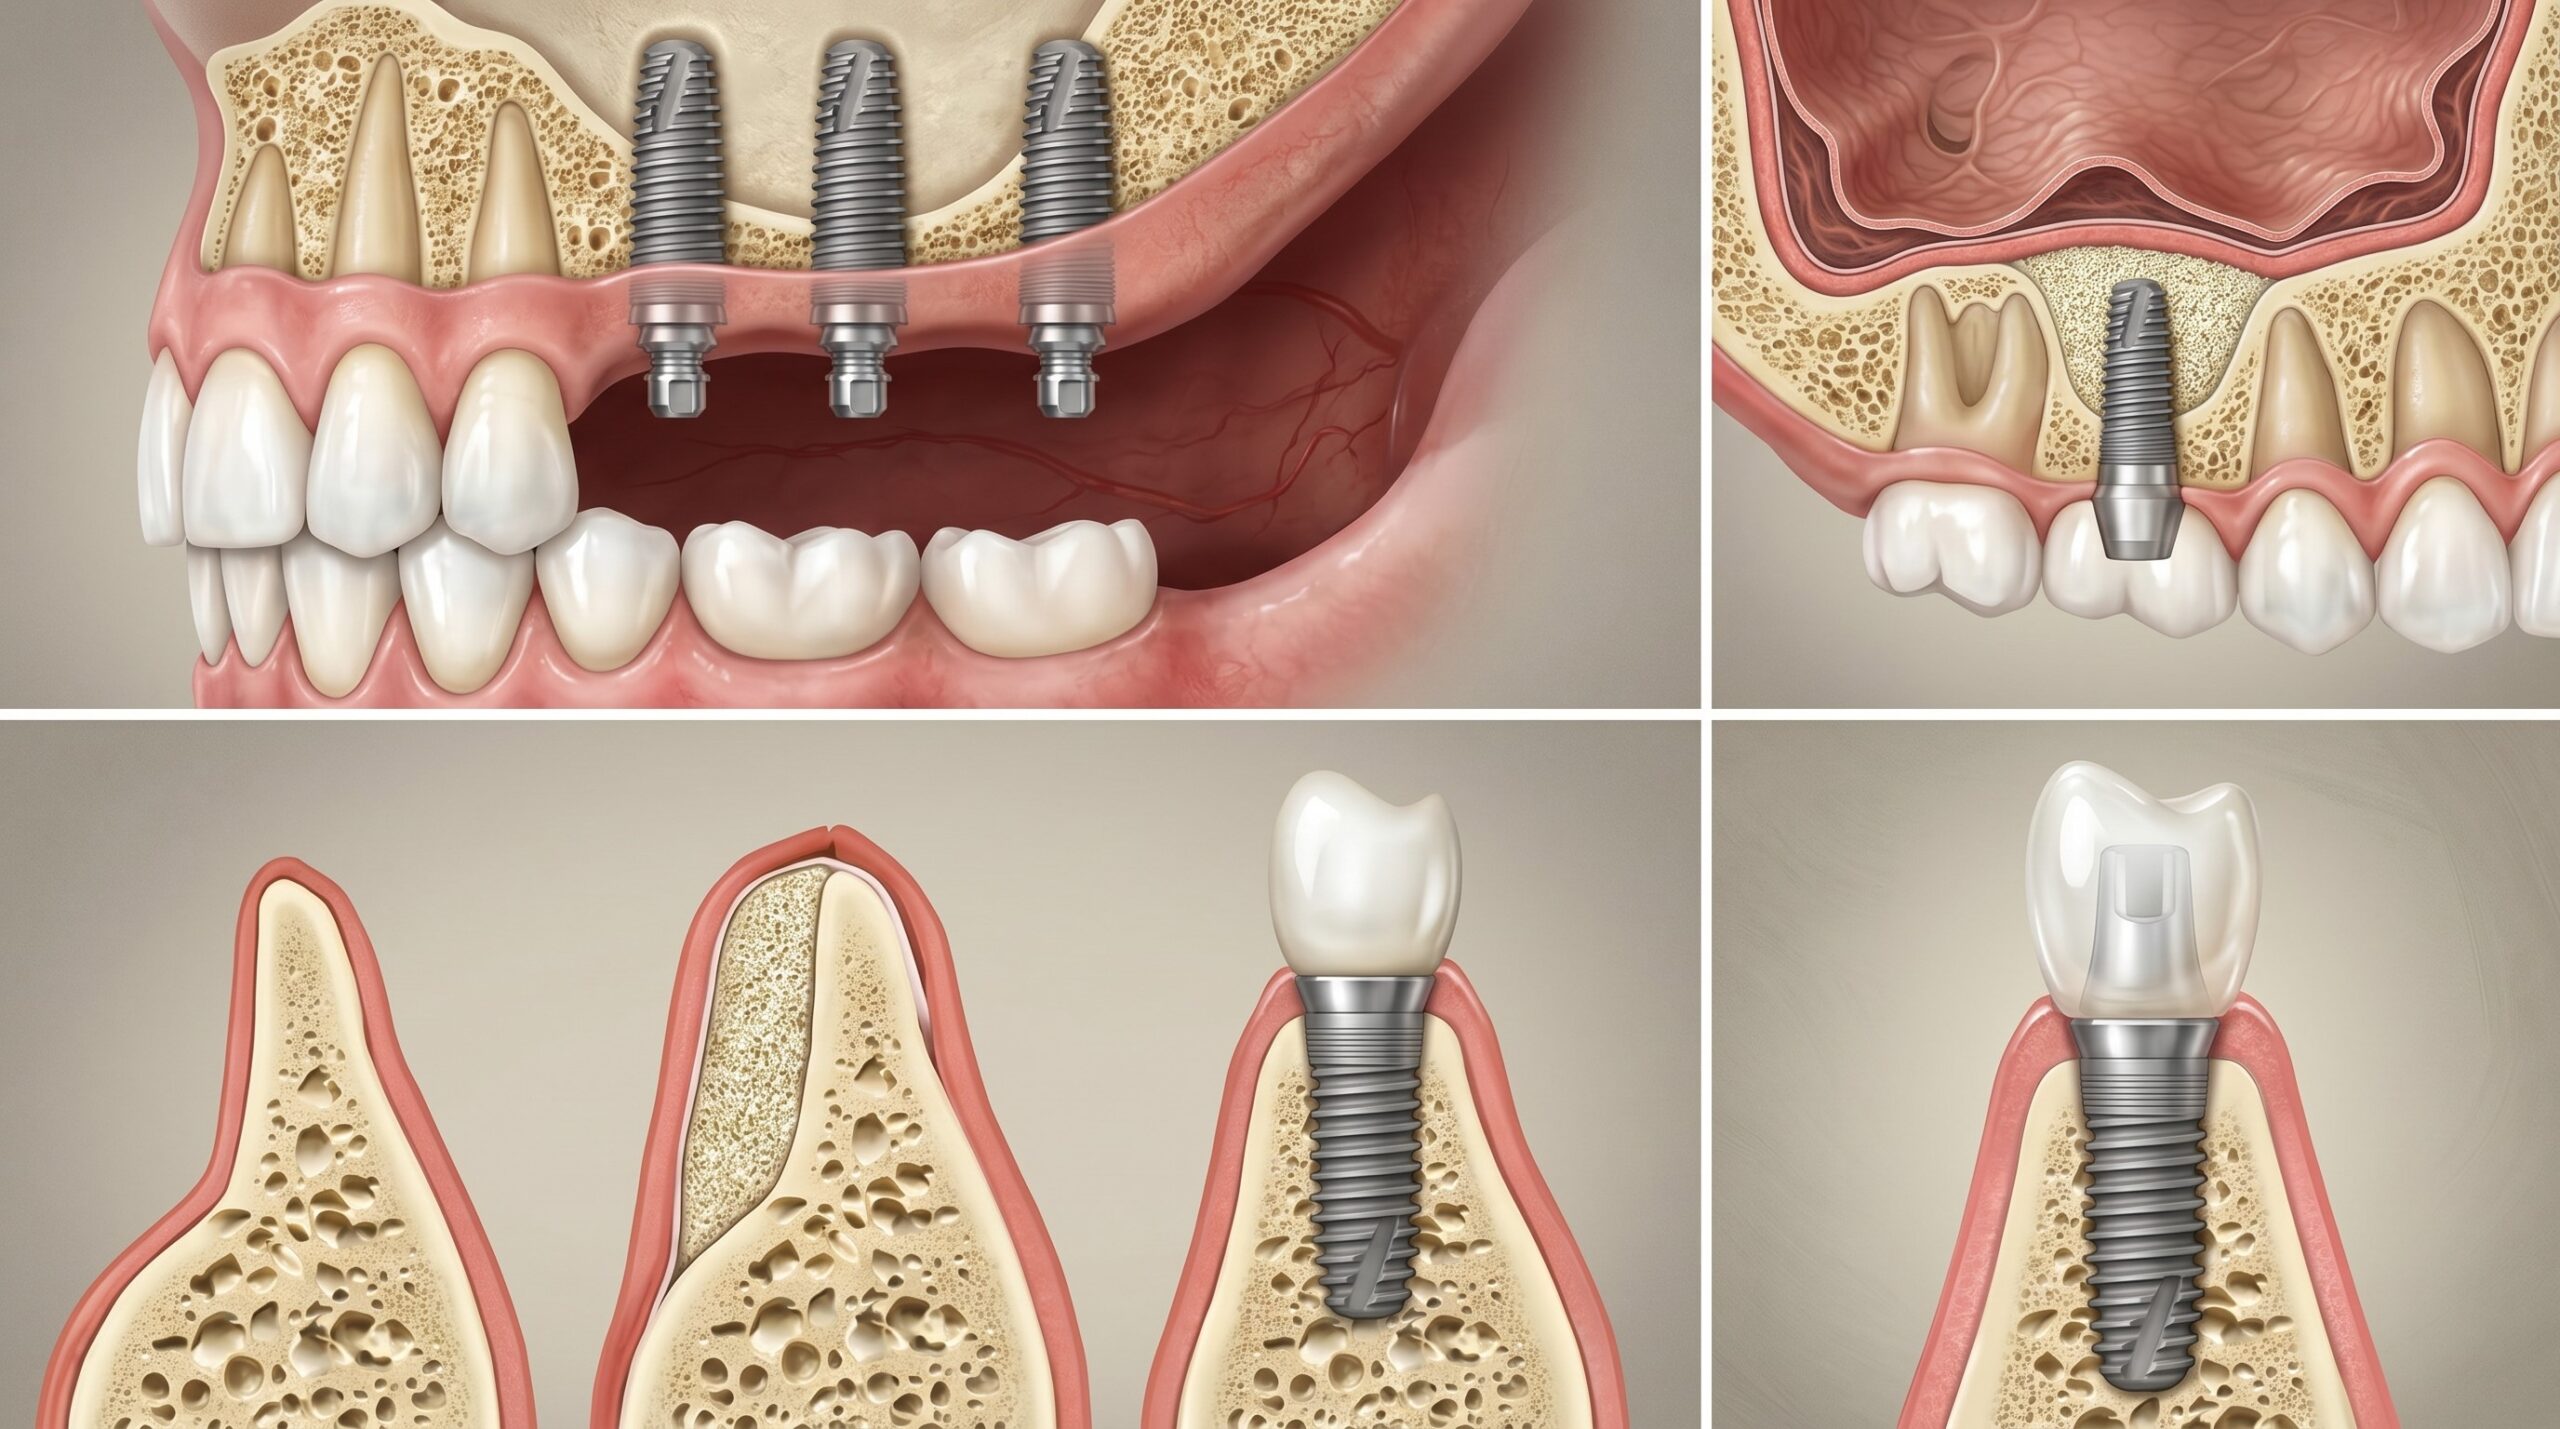

뼈이식에 사용하는 재료는 크게 자가골(환자 본인의 뼈), 동종골(조직은행 뼈), 이종골(주로 소 유래), 합성골(인공합성 재료) 네 가지로 나뉩니다. 각각의 흡수율과 골유도 능력이 다르기 때문에, 결손 부위의 크기와 위치에 따라 단독 또는 혼합하여 사용합니다. 서울인플란트치과에서는 자가혈(혈소판 풍부 피브린, PRF)을 함께 활용하여 골재생을 촉진하고 회복 기간을 단축하는 방법을 적극적으로 적용하고 있습니다.

가장 많이 받는 질문 중 하나입니다. 결론부터 말씀드리면, 뼈이식을 동반한 임플란트의 전체 치료 기간은 최소 4개월에서 최대 9개월까지 달라질 수 있습니다. 소규모 뼈이식과 임플란트를 동시에 진행할 수 있는 경우라면 4~6개월이면 보철까지 완성되지만, 뼈이식 후 골이 충분히 재생되길 기다렸다가 임플란트를 심어야 하는 대범위 결손의 경우 6~9개월이 소요됩니다. 상악동 거상술은 외측 접근 시 최소 6개월의 골유합 기간이 필요합니다.